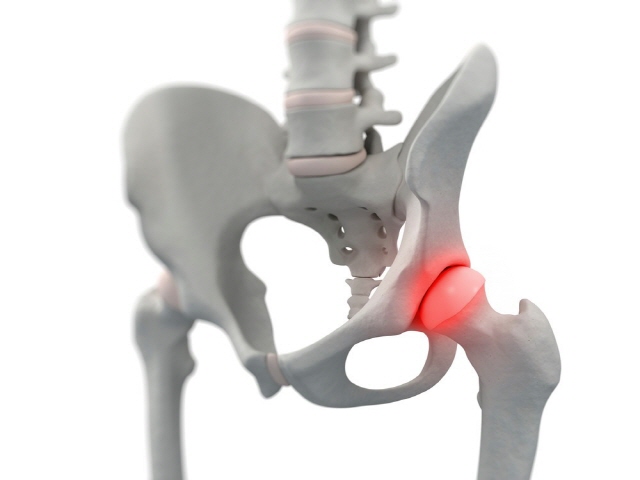

이 증상은 퇴행성 고관절염에 의해 발생되는 현상으로 일반적으로 중장년층에게 자주 일어나는 질병인데요. 이 질병은 관절과 관절 사이에 존재하는 연골이 닳아 없어지면 관절 내부와 주위에 염증과 통증을 동반해요.

보통 골반 아래에 뻐근한 증상을 일으키고 양반다리 자세를 할 때 통증이 심해져요. 뿐 아니라 계단을 오를 때 통증이 심해지고 오래 걷는것도 힘들어 져요.

고관절 통증 증상 - 퇴행성 고관절염

퇴행성 고관절염인 경우에는 뼈사이 간격이 없어요. 연골이 마모되고 노화가 진행되면서 퇴행성 고관절염이 발생해요.